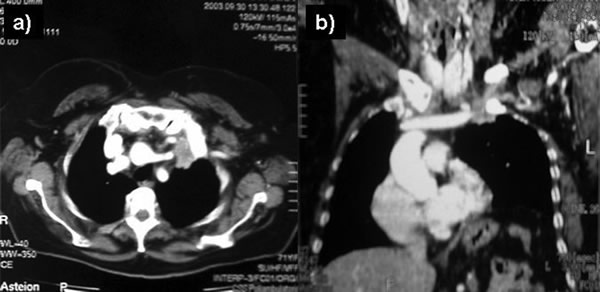

The subclavian artery can usually be dissected through the subadventitial plane (Video 8). Local branches (e.g., the internal mammary artery, thyrocervical trunk, or occasionally the vertebral artery) should be identified and transected if necessary. If the subclavian artery is invaded by tumor (Figure 10), the involved segment can also be resected and reconstructed through a posterior approach (Figure 11). After systemic heparinization, the artery is cross-clamped proximally and distally excluding the invaded segment and revascularized using either an end-to-end anastomosis or, more commonly, the interposition of a polytetrafluoroethylene (PTFE) graft, 6 to 8 mm in diameter (Video 9).

| Figure 10. Chest CT-scan shows the invasion of the subclavian artery by Pancoast tumor. | Figure 11. The invaded artery was resected and replaced by a PTFE graft through a posterior approach. |